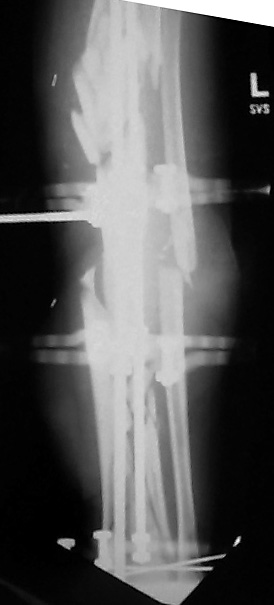

Date: Thu, 14 Dec 1995 17:48:46From: hwb@eideti.com (Bill Burman)Of course what I have to say has to be taken with a mountain of salt as Ihave not practiced orthopaedics for 5 years.What I would do at this point is hike out the 5 mm diaphyseal pin. I can'tbelieve it is doing much. I would wait a few more weeks for that pin tractto properly clean itself and seal up. Hopefully it has not been infected.At that time I ought to have pretty good consolidation of themetaphyseal-epiphyseal fractures. I would remove from the ends of the boneany hardware which would block the placement of a reamed interlockingtibial nail. Large reduction forceps and possibly strategically placedsteinman pins would be used to protect against the possibilty ofmetaphyseal-epiphyseal refracture during nail placement. The nail needs tobe carefully started as high as possible and more lateral than usualbecause of a valgus tendency for nailings of proximal tibia fxs.If at this time, I did not see much in the way of diaphyseal callus thenprior to nail placement, I would try to do a closed intramedullary iliacbone grafting with chest tube ala Chapman, JBJS 62A 1004 1980. I realizethis technique was meant for segmental defects of the femur but this mightbe an application for it as well. If I couldn't get much graft in this way,I would put it in posterolateral - if that did not jeopardize the free flapin some way.*****************************From: EDCCYANG@aol.comDate: Thu, 14 Dec 1995 22:16:30 -0500You are to be commended for what you've done so far. It sounds like thetibia is well aligned and the soft tissues are healed. Now you just have toget the bones healed.I have extensive experience with the hybrid exfix but never have I seen atibia this shattered. (or maybe once)Now I would try the exogen unit, if you have not done so already. This isthe ultrasound device which has been working great for us! Their telephone# is 1-800-836-0849.I would hold him in the external fixator as long as the pins are clean.Hopefully, some of the fractures will heal and you can deal with only one ortwo nonunion sites. Consider plating the fibula and getting the fibulahealed, either simultaneously with a fib-pro-tib operation, and /orposterolateral bone graft. I have done all of the above to get tibiae toheal.Edward Yang, MDElmhurst HospitalMount Sinai****************Date: Fri, 15 Dec 1995 10:21From: Jeffrey Anglen Bill, for a guy who hasn't practiced clinically for 5 years, you seem tohave a pretty good grip on treating tibia fractures. The only thing I woulddisagree with is conversion to an intramedullary nail after this period oftime. I would be too afraid of intramedullary infection from a pin site,even if the pin sites looked OK. I don't know if the risk is the same withhybrid fixators as it is with traditional half-pin fixators - that might makean interesting study - perhaps someone with more experience withhybrid fixators has a better feel for the relative risk between pin andwire sites.I would continue with hybrid fixation, a little weightbearing and earlybone graft of the diaphysis posterolaterally. I have no experience withthe accordion technique.How about you guys at Harborview? Any thoughts on this tibiafracture?****************Date: Sat, 16 Dec 1995 11:45:10 +0530 (IST)From: "Dr.ML Parihar" the accordion manouevre does not work. to my knowledge this is nowuniversally accepted, especially in the treatment of non-unions. anyonedisagree?for a comminuted fracture of the tibia why not consider atibia-pro-fibula grafting as described by harmon. while on the subject ofbone grafting i would like to hear fromsurgeons who have used bone marrowinjections for the treatment of nonunion or delayed union.how much to be aspirated? from where?where do you inject? into the fracture site or in a cuff fashion aroundthe fracture site? Dr. Mangal Parihar**************************Date: Sat, 16 Dec 95 22:04:09 +0500From: "Alexander N. Chelnokov" Hi> I have not received any further comments/suggestions on the comminuted> tibia case since posting the images of the xrays. There has been> considerable useful discussion of posting images to be easily viewed> in various manners.Sorry but I missed when you pointed the name and location of the image so plsrepeat...> I did institute the "accordion" technique of .25 mm compression at> 6 am and noon; then .25 distraction at 6 pm and midnite.We use another schedule - 2 weeks of distraction 0.5mm/day and then2 weeks of compression 1 mm/day...> I also started 10 pound weight bearing.I do not limit weigth-bearing. More exactly, patient should load his legas he can. In case of extra-articular fractures of course.> I'd like to bone graft it but I'm not sure> where to put the bone graft because there are so many pieces.Do think about marginal corticotomy and slow tension of fragments to bridgegaps?*************************Date: Sun, 17 Dec 95 21:45:18 -0600From: "Andrew H. Schmidt" After seeing the images, I congratulate Tom on his management of the casethus far. Our general philosophy at Hennepin County is that once externalfixation is chosen as the treatment, it should be continued to union. Whenpossible, we will convert to a nail within the first couple of weeks, butnot beyond this because of the concern for infection.In my experience with either plateau or plafond fractures plus diaphysealextension, the metaphyseal fractures heal and it is the diaphysealcomponent that requires grafting. I have several times removed the hybridfixator, curretted the pin sites, performed an open autogenous grafting,and reapplied a new half-plane unilateral fixator to the diaphysis. Ofcourse, if the hybrid frame was still needed I would not replace it.However, I find the circular hybrid frames to be such a hassle to take careof, and the patients dislike them so much, that if the juxta-articularfractures are healed, I go ahead and convert to a simpler fixator. So, that remains my two-cents worth, which I thought I'd post to the wholegroup this time since this case has sparked so much interest.AndyAndrew H. Schmidt, M.D.Staff Physician, Hennepin County Medical CenterClinical Instructor, University of Minnesota******************************Date: Tue, 19 Dec 1995 12:31:57 -0500From: hwb@eideti.com (Bill Burman) I see from the discussion that perhaps I am too aggressive and need tolearn how to relax.I am learning some new things here. Dr. Ed Yang made a plug for ultrasoundstimulation - Exogen. Here is the abstract of an article published in theJ Bone Joint Surg Am 1994 Jan;76(1):26-34 by the San Antonio group(Heckman, Ryaby, McCabe J, Frey JJ, Kilcoyne RF). The study was paid forby Exogen.TI - "Acceleration of tibial fracture-healing by non-invasive, low-intensity pulsed ultrasound."AB - "Sixty-seven closed or grade-I open fractures of the tibial shaft were examined in a prospective, randomized, double-blind evaluation of use of a new ultrasound stimulating device as an adjunct to conventional treatment with a cast. Thirty-three fractures were treated with the active device and thirty-four, with a placebo control device. At the end of the treatment, there was a statistically significant decrease in the time to clinical healing (86 +/- 5.8 days in the active-treatment group compared with 114 +/- 10.4 days in the control group) (p = 0.01) and also a significant decrease in the time to over-all (clinical and radiographic) healing (96 +/- 4.9 days in the active-treatment group compared with 154 +/- 13.7 days in the control group) (p = 0.0001). The patients' compliance with the use of the device was excellent, and there were no serious complications related to its use. This study confirms earlier animal and clinical studies that demonstrated the efficacy of low-intensity ultrasound stimulation in the acceleration of the normal fracture-repair process."Also, Dr. Parihar mentions bone marrow injection. In CORR 313 8-18, 1995,Dr. John Conolly of Orlando, FL writes :TI - "Injectable Bone Marrow Preparations to Stimulate Osteogenic Repair."AB - "The great versatility of bone marrow transplants based on stem cellactivity has been demonstrated successfully for a variety of previouslyuntreatable hemopoetic conditions. Autologous bone marrow delivered bypercutaneous injection or by a direct transplant as a composite graft alsohas proven effective for osteogenic stimulation in a series of 100 skeletalhealing problems, including delayed unions and nonunions of fractures,arthrodeses, and bone defects. The efficiency of marrow to form bone can beincreased by a number of methods, including differential centrifugation andcomposite grafts of marrow with demineralized bone matrix and othercarriers or stimulatory factors."Dr. Connolly concludes his article by saying :"Marrow and marrow composite grafts, in this author's experience during thepast 8 years, essentially have eliminated the need for open harvesting anddelivery of autologous bone grafts to stimulate osteogenic repair ofdelayed unions, nonunions, arthrodeses and bone defects."Any references for the Ilizarov "accordion maneuver"?***************************Date: Tue, 19 Dec 1995 14:11:27From: hwb@eideti.com (Bill Burman)I am transmitting another opinion received via the HWB BBS fromDr. Joldas KuldjanovVisiting Professor at Detroit Medical CenterProfessor of Orthopedics & TraumaUniversity of Tashkent, UzbekistanRe: comminuted tibia fxThus far, there appears to be no sign healing because of local factors, thehigh energy of trauma, stripping of periosteum, soft tissue damage and poorcontact of bone. I would have initially fixed the fracture with a four ringIlizarov fixator. 2 rings in metaphyseal zones (distal and proximal) and 2rings in the diaphyseal region for the purpose of interfragmentarycompression.The location of wound and soft tissue damage is unknown to me. It is mostlikely anteromedial ?At this point, I would perform open reduction and internal fixation offibula with a long semitubular plate. I would add 2 more rings to thefixator to bring about reduction and interfrag compression of the tibialcomminution. The type of fixator is immaterial but interfrag compressionwould be accomplished by olive wires. Also, I would add bone graft andplacement of this would be in accordance with the location of soft tissuedamage. Weight bearing should be as tolerated and there should be cautionabout the possibity of equinus. I am not too worried about pin tractinfection. These smaller pins can be easily replaced. I would use theaccordion technique in the event of atrophic non-union.Best regards and best wishes with the management of this very difficult case.***********************Date: Tue, 19 Dec 1995 22:03:13 -0500From: OTS1@aol.com RoyI am somewhat amazed at all this discussion, but find it fascinating. Iwould treat this guy to completion with the circular frame until thearticular and metaphyseal components healed. Unfortunately, you would get amal-/non-union at the diaphysis which would preclude the use of a later nail,unless you took it all down. If you needed to do that I would then just platehim with a long 18 - 22 hole 4.5 narrow DC plate on the medial side. Thiswould obviate the risk for infection. Furthermore you could graft at the timeof plating. So what's the big deal? Routine case,... right?Anyway, Exogen is too new to try, and Connally's study is severely flawed,too many variables, no controls, hypertrophic nonunions rodded and thenmarrow injected, nonunion healed. Don't you think it would have healedwithout the injection? Of course it would have! Anyway, I like this format.Anyone going to Russia?***************************From: "Alexander N. Chelnokov" Date: Wed, 20 Dec 95 06:51:16 +0500Hi> Also, Dr. Parihar mentions bone marrow injection. In CORR 313 8-18, 1995,> Dr. Connolly concludes his article by saying :>> past 8 years, essentially have eliminated the need for open harvesting and> delivery of autologous bone grafts to stimulate osteogenic repair of> delayed unions, nonunions, arthrodeses and bone defects.";) Told like about Ilizarov.> Any references for the Ilizarov "accordion maneuver"?I used it last years... It really works.But for the case maybe better would be to add partial corticotomies andperform closed slow "bridging" by the fragments.About reference... This must be accessible for you:TI: Clinical application of the tension-stress effect for limb lengthening.AU: Ilizarov-GAAD: Kurgan All-Union Center for Restorative Traumatology andOrthopaedics, USSR.SO: Clin-Orthop. 1990 Jan(250): 8-26AB: For 40 years, the author has been developing a system oforthopedics, traumatology, and limb lengthening using a circulartransfixion-wire external skeletal fixator, often in combination withbiomechanic methods of stimulating the formation of new osseous tissuewithin a widening osteotomy distraction site. The factors important forneoosteogenesis after osteotomy include: maximum preservation ofextraosseous and medullary blood supply; stable external fixation; adelay prior to distraction; a distraction rate of 1 mm per day infrequent small steps; a period of stable neutral fixation afterlengthening; and physiologic use of the elongating limb. For asuccessful fixator application, the apparatus must be applied withconsideration given to the number, size, and location of the rings, theplacement and tension on the wires, the technique of wire insertion, theeffect of soft-tissue transfixion on limb use, and the prevention ofbone and joint deformities caused by countertension in soft tissues.Clinical application of the author's techniques permits stature increasein certain forms of dwarfism, correction of deformities and limb-lengthinequalities, and stump elongation. For many of these applications,motorized distraction can provide continuous limb lengthening while theapparatus is on the patient. Best regards, Alexander N. ChelnokovUral Scientific Institute of Traumatology and Orthopaedicsstr.Bankovsky, 7. Ekaterinburg 620014 Russia********************Date: Thu, 21 Dec 1995 12:46:14 +0530 (IST)From: "Dr.ML Parihar" On Wed, 20 Dec 1995, Alexander N. Chelnokov wrote:> > Any references for the Ilizarov "accordion maneuver"?>> I used it last years... It really works.> TI: Clinical application of the tension-stress effect for limb lengthening.> AU: Ilizarov-GAfor a start lets try to define what we mean by the 'accordion maneuver'.i have heard it used to talk about alternating cycles of compressiondistraction in the same day, compression for a preiod of 1 or more weeksfollowed immediately by distraction for an equal duration; and also forcompression followed by a rest period and then a period of distraction.though the articles from kurgan talk about successes with the 'accordionmaneuver', most other surgeons that i have had occasion to meet eitherpersonally or at meetings have not found it to be a useful maneuver inatrophic nonunions which is what it 's use is advocated for.i personally have not had any experience with it. Dr. Mangal Parihar************************Date: Sat, 23 Dec 95 10:52:54 CSTFrom: kenneth.d.johnson@mcmail.vanderbilt.eduThis message was originally written on Dec.18, who knows where it has been?Congratulations on a job well done to date. Hopefully the leg is straight and clean, and the proximal metaphysis fracture is now healed. Now comes the time to think! I agree with others, a nail would not be advisable at present. Perhaps the ultrasound would help, it certainly shouldn't hurt! No experience here. Personally, I think the fixator and posterolateral bone grafting is your best bet. With the proximal fracture you would have to arthrodese the proximal tib-fib joint. I can't appreciate the x-ray well enough to see how far down the bone graft would need to go but you could go as far as the distal tib-fib joint. Perhaps within 6-8 weeks of grafting you could consider removing the fixator and using a cast. Also if the amount of graft is a question or better a problem, one could consider the use of Colagraft to augment the usual autogenous cancellous bone graft.I can say though that I am glad that it is you and not me!KDJ ***********From: hwb@eideti.com (Bill Burman)Date: 12/21/95 6:58 PMAlexander,Maybe I am missing something but I have re-read :>TI: Clinical application of the tension-stress effect for limb lengthening.>AU: Ilizarov-GA>AD: Kurgan All-Union Center for Restorative Traumatology and>Orthopaedics, USSR.>SO: Clin-Orthop. 1990 Jan(250): 8-26and cannot find specific reference to the efficacy of the "accordion"technique for atrophic nonunion. Are there any series in the Russianliterature which compare the "accordion" technique to controls or othertreatment methods of nonunion ?************************Date: Wed, 20 Dec 1995 18:34:33 -0700 (MST)From: TDECOSTE@medusa.unm.eduI'd like to get Dr. Kuldjanov's email address but can't decipherit from the message I received.His suggestion for additional diaphyseal wires and rings is mostappealing to me but I'm not sure which pieces of diaphysealcomminution would be appropriate.Tom DeCoster. Merry Christmas****************************Date: Sat, 23 Dec 1995From: hwb@eideti.com (Bill Burman)In reply to Dr. Tom Decoster's request for more specifics, Dr. Joldas Kuldjanov from Detroit Medical Center has faxed to the HWB Foundation a diagram of a preoperative plan illustrating the placement of additional rings and olive wires for posting with the discussion of this case at :http://www.hwbf.org/hwb/

Click images to enlarge.